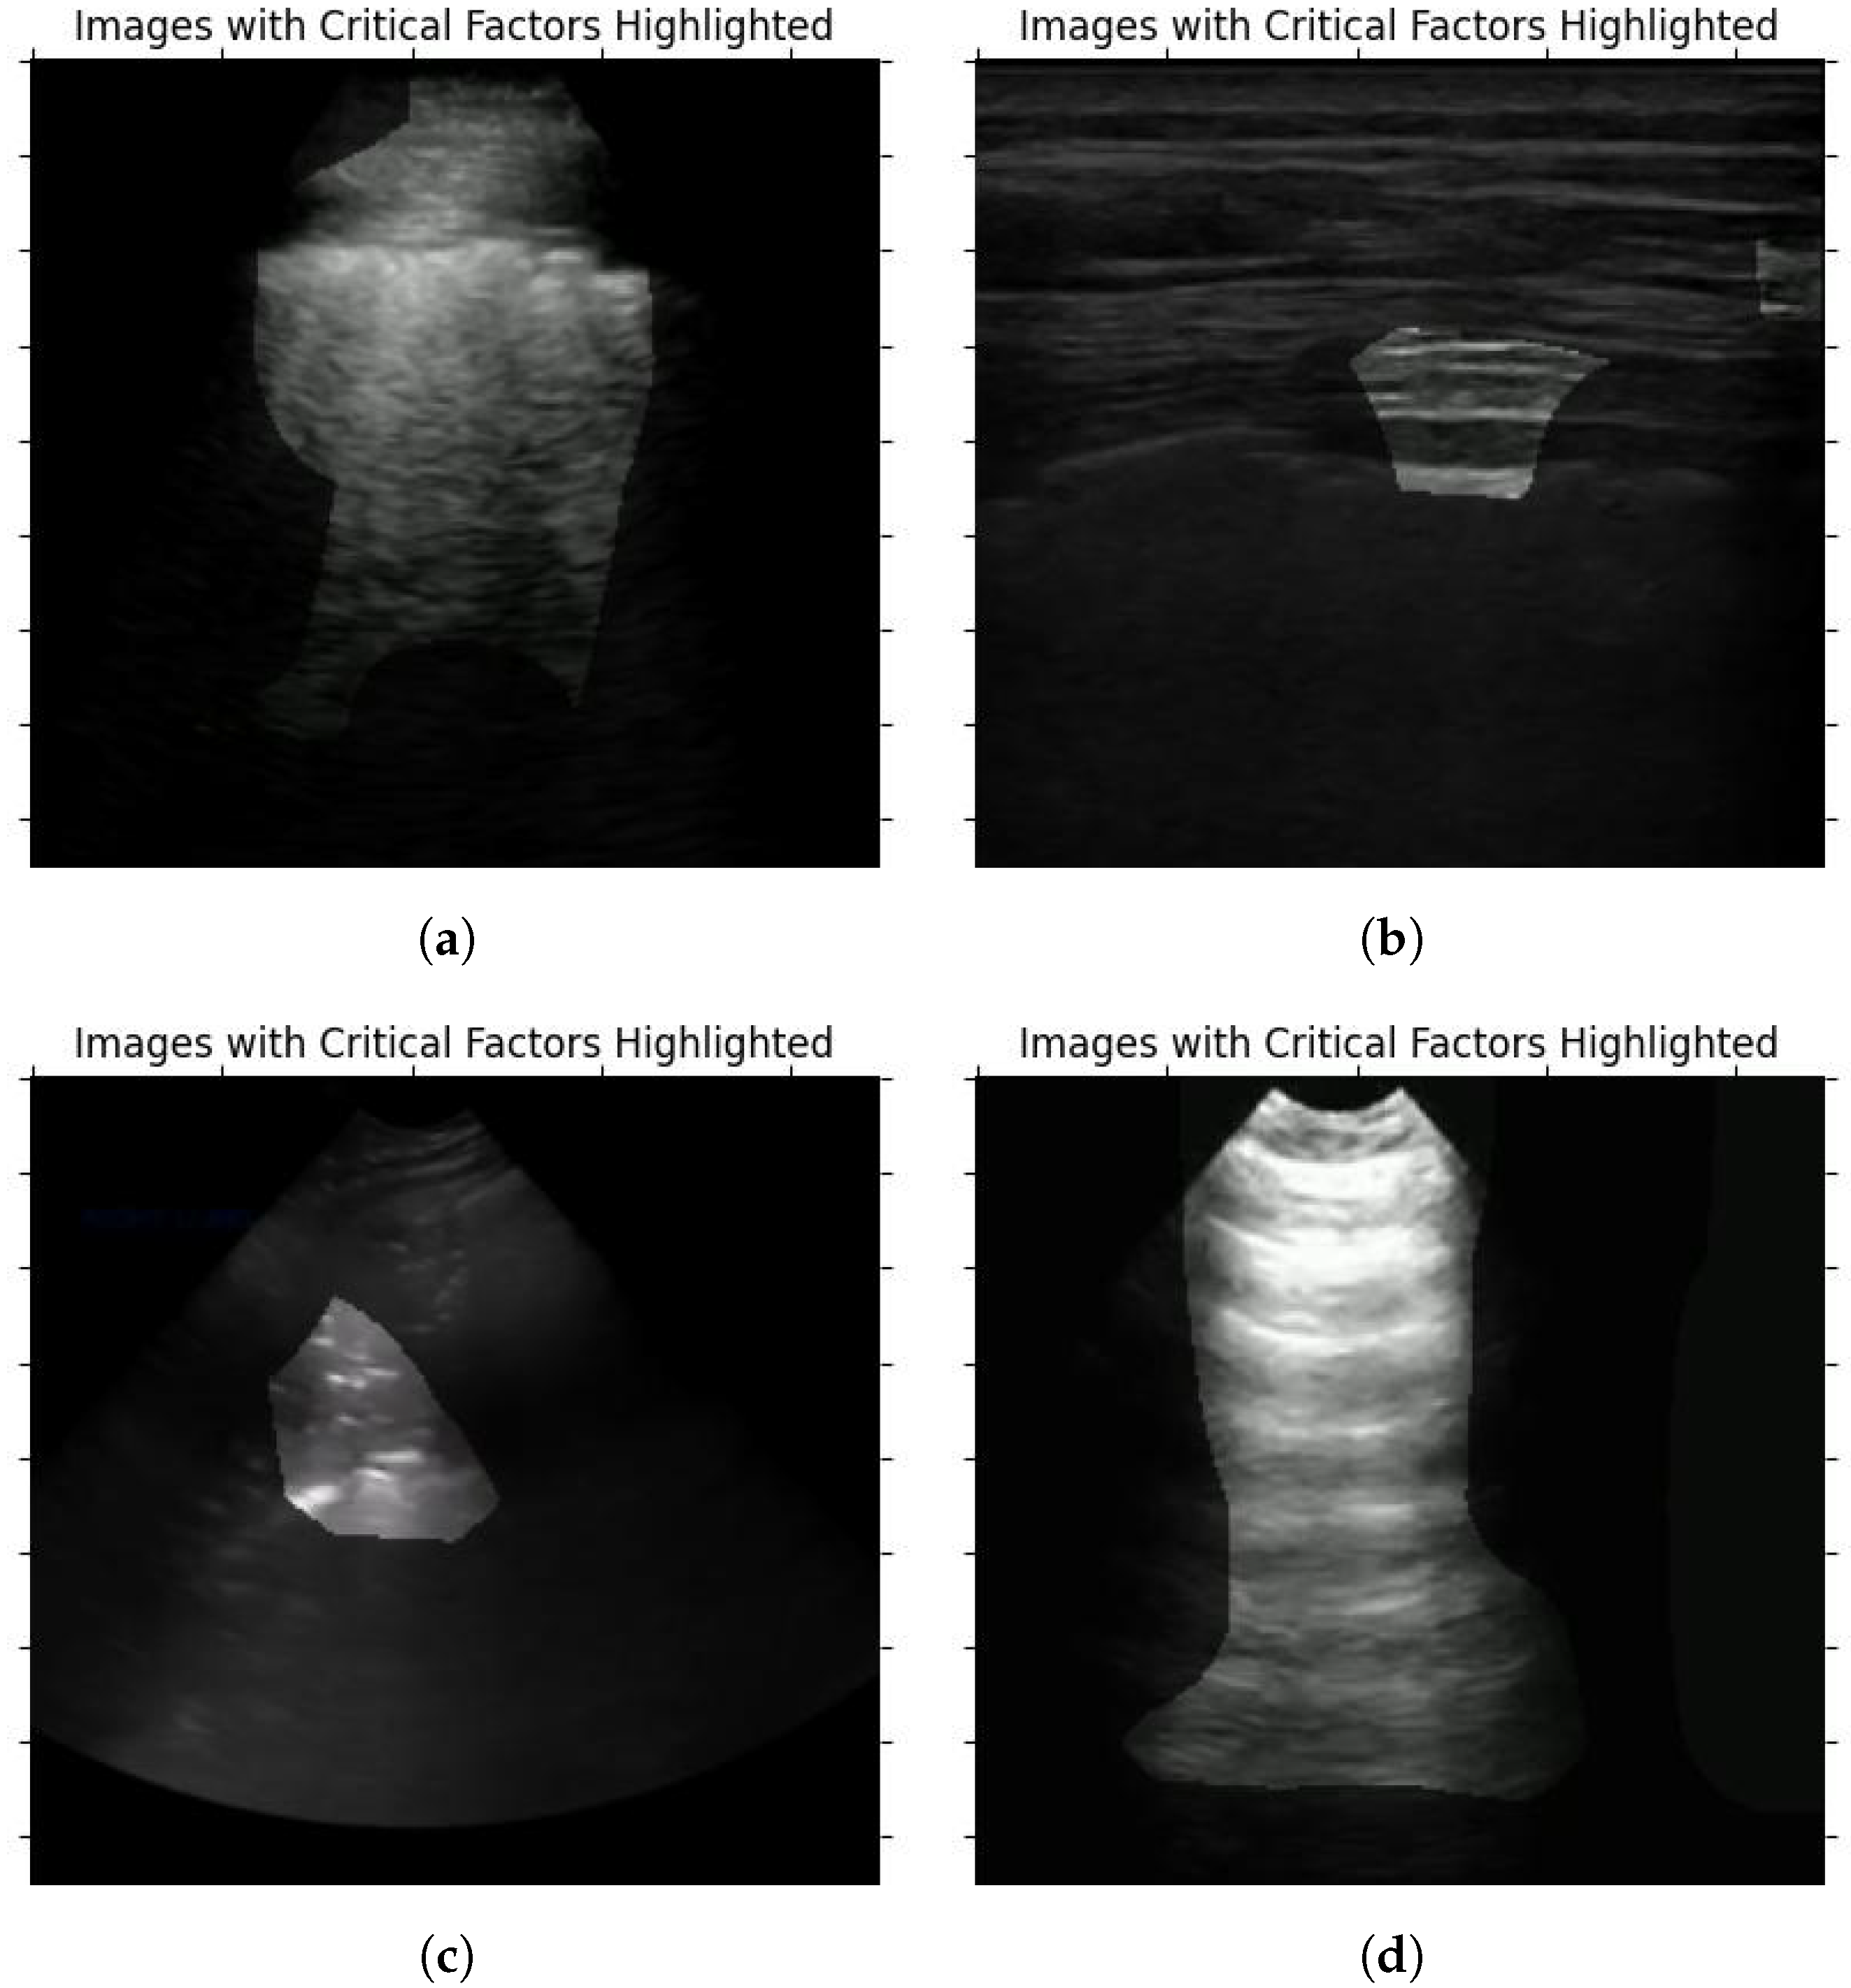

As explained in Section 4, to confirm the viability of the COVID-Net L2C-ULTRA prediction results, we apply GSInquire [38] to the ultrasound image inputs. Our contributing clinician (A.F.), who possesses expertise in ultrasound image analysis, randomly reviewed the outcomes of GSInquire annotation and reported his findings and observations. This assessment aimed to determine whether the network effectively and reliably captures clinically important patterns. Our contributing clinician (A.F.) is an Assistant Professor in the Department of Emergency Medicine, and serves as the ultrasound co-director for undergraduate medical students at McGill University. He is practicing Emergency Medicine full-time at Saint Mary’s Hospital in Montreal. He was provided with the results of the proposed model on test set to confirm its validity. Of the images reviewed, four examples, shown in Figure 7, were chosen as examples to demonstrate the model’s performance on COVID-19, pneumonia, and normal annotated images. The summary of our expert clinician’s report is as follows.

Case 1 (Figure 7a). This image demonstrates the presence of b-lines throughout the scanned window which is assumed to be an intercostal space. The pleura appears to be broken and irregular and there is a suspicion of subpleural consolidations. In the appropriate clinical context, this appearance would be one of the classic lung ultrasound presentations of COVID-19.

Case 2 (Figure 7b). In this image, it is not very clear what GSINquire is focusing on and another frame from this clip would be needed to make a better interpretation. Nevertheless, the pleural and subpleural region emerges as the pivotal element. Considering the peripheral location of COVID-19 lesions within the lungs, this area precisely aligns with our anticipation of locating pathological indicators.

Case 3 (Figure 7c). This image denotes lung hepatization and a classic appearance of consolidated lung, which is a feature of pneumonia.

Case 4 (Figure 7d). This image denotes the classic appearance of the lung on ultrasound with the presence of the pleura and the artifacts called a-lines, which are present in normal lungs.

The observations and findings from our expert clinician substantiated the presence of pertinent artifacts and markers associated with lung diseases, such as consolidations and b-lines, along with indicators of healthy lungs, confirming the reliability of COVID-Net L2C-ULTRA in capturing clinically relevant features.

Figure 7. Sample ultrasound images, annotated by GSInquire, reviewed and reported on by our contributing clinician. (a) COVID-19 example; (b) COVID-19 example; (c) pneumonia example; (d) normal example.